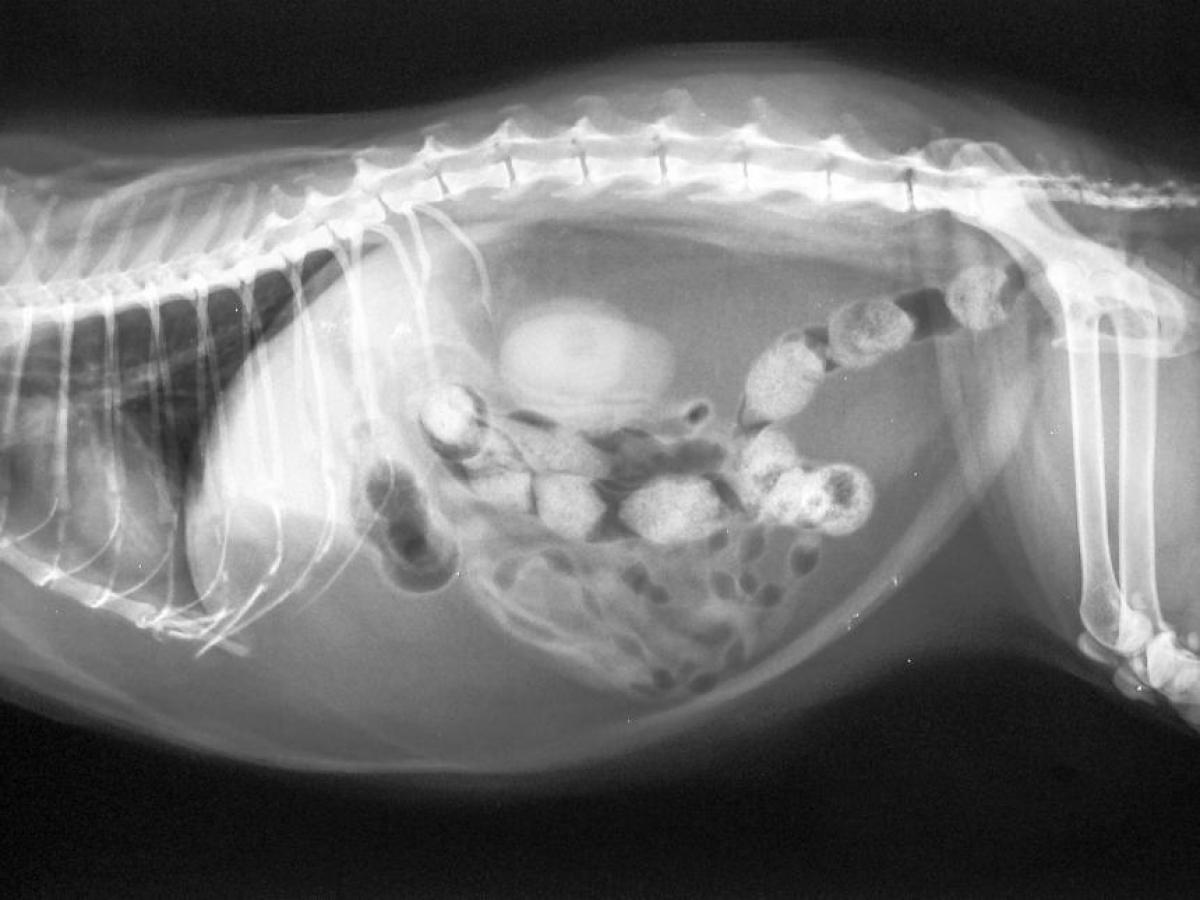

- Digital radiology (x-rays)